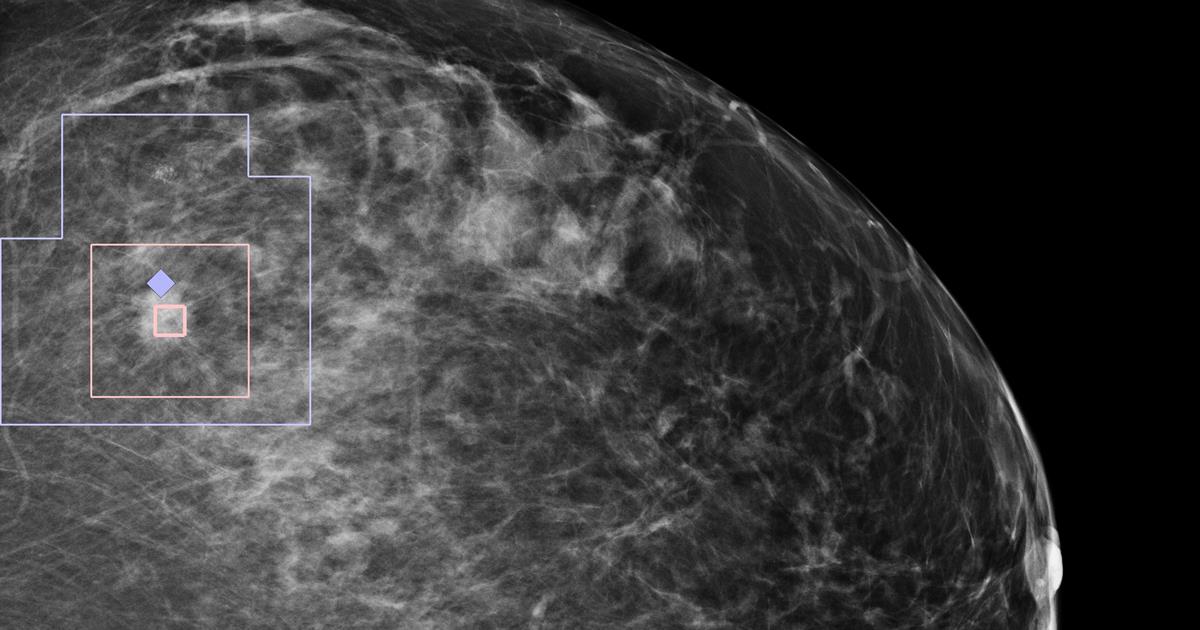

Компания Zebra Medical Vision объявила о получении официального разрешения европейских регулирующих органов на использование нового алгоритма, предназначенного для ее платформы Deep Learninng Imaging Analytics. Этот алгоритм предоставляет возможность автоматически распознавать подозрительные злокачественные очаги в маммографических сканах и является последним дополнением в линейку автоматических инструментов обработки медицинских изображений AI1 (All-In-One). В этот пакет входят алгоритмы, которые способны обнаруживать кровоизлияния в мозг, переломы позвоночника, заболевания коронарных артерий, остеопороз и др.

Новый алгоритм на базе искусственного интеллекта компании Zebra Medical Vision предназначен для изменения этой ситуации, предоставляя очень качественный инструмент обнаружения злокачественных опухолей в груди по существенно более низкой цене. Первая версия этого алгоритма, которая была недавно выпущена компанией, поддерживает устройства 2D Hologic. Но, по словам специалистов Zebra Medical Vision, в течение 2019 года они смогут добавить в него возможность работы с приборами других производителей, а также 3D-поддержку.